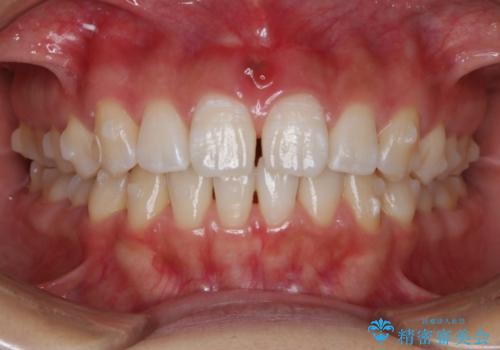

インビザライン矯正 前歯のすきっ歯を治したい

- 上顎の前歯のすきっ歯を治したいとのことで来院されました。

前歯の隙間を閉じる矯正治療の場合、インビザライン適用症例のためインビザラインによる治療をご提案しました。

後戻り防止のため、上唇小帯切除も併用しています。

上唇と歯ぐきを結ぶひも(上唇小帯)が長いと、前歯に隙間が空いてしまうことがあります。今回は隙間を確実に閉じる目的、また矯正後に再び隙間が空かないように、上唇小帯の切除も行っています。